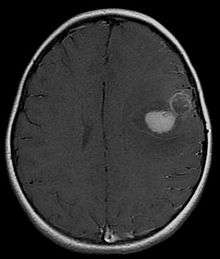

Primitive neuroectodermal tumor (PNET) is a malignant (cancerous) neural crest tumor.[1] It is a rare tumor, usually occurring in children and young adults under 25 years of age. The overall 5 year survival rate is about 53%.[2]

It is classified into two types, based on location in the body: peripheral PNET and CNS PNET.